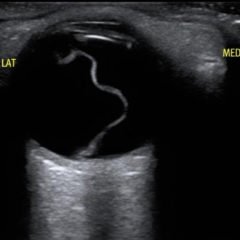

Bedside ultrasound with the phased array probe was used to obtain a parasternal long axis view which demonstrated poor contractility and a severely decreased ejection fraction (EF). M-mode was placed over the anterior leaflet of the mitral valve to create a tracing depicting both the E-wave of early diastole (green arrow) and the A-wave from the atrial kick (blue arrow). The shortest distance between the septum and the mitral valve on the M-mode tracing gives the patient’s E-Point Septal Separation (EPSS) (pink arrow). EF can be estimated using the formula EF=75.5-2.5 x EPSS (in mm). This patient’s EPSS was measured to be 20mm which estimates that she had an EF of 25.5%.